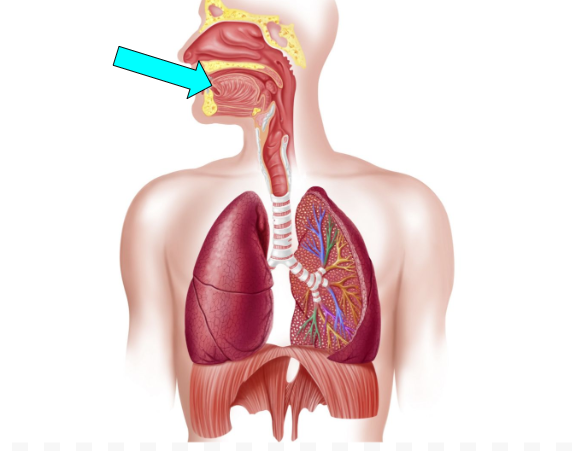

Oral Cavity (pic)

Pharynx (pic)

Epiglottis (pic)

Larynx (pic)